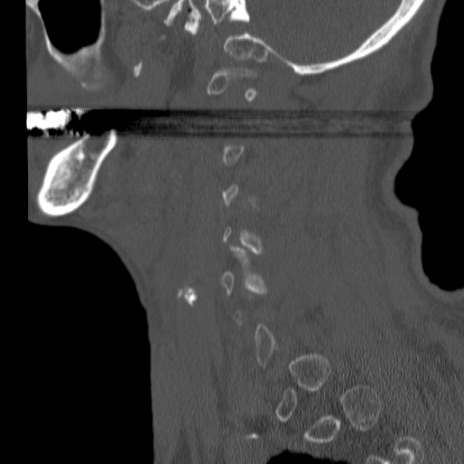

症例46 頚椎CT(矢状断像)

【症例】80歳代男性

【主訴】両側頚部〜上肢のしびれ

【現病歴】昨日、自宅内で転倒、その後より上記症状あり。意識障害なし。

【身体所見】両側上肢のallodynia(熱痛覚過敏)あり。MMTおよびDTRは正確な所見取れず。両上肢の挙上はなんとか可能。

異常所見と診断は?